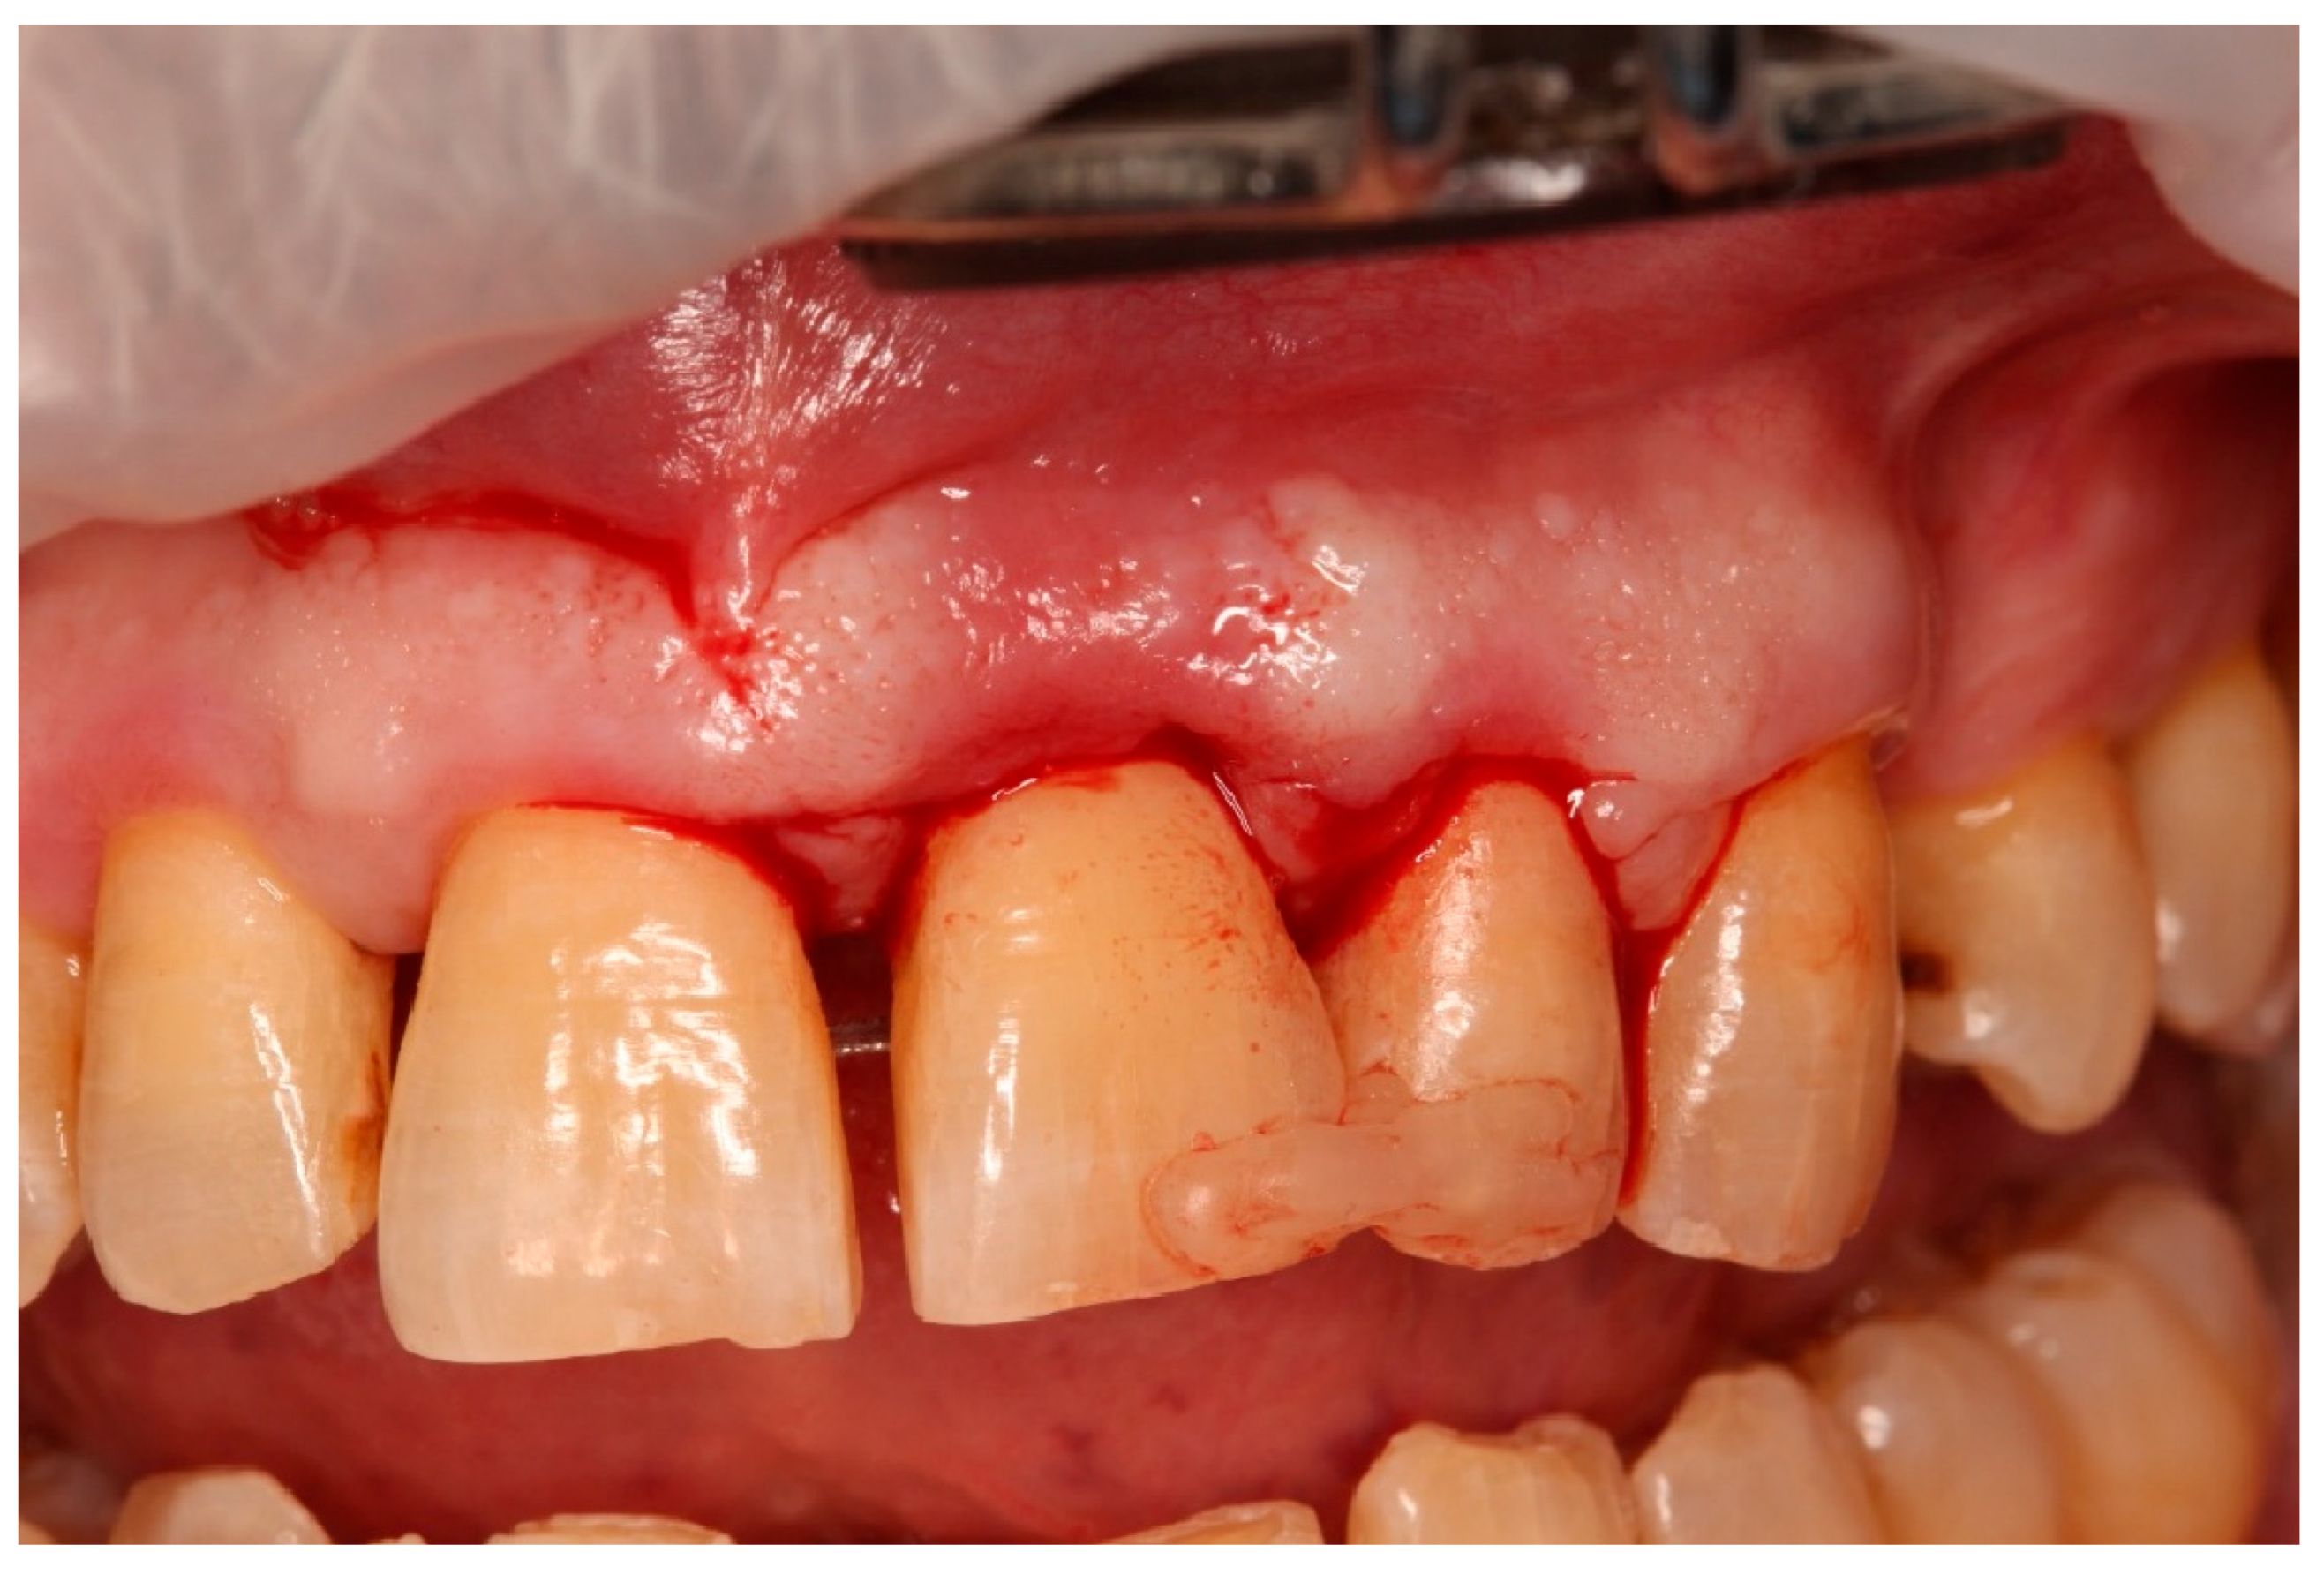

- Atraumatic extraction: Tooth 21 was carefully luxated using periotomes to preserve the PDL and surrounding bone. Immediately after extraction, the tooth was stored in chilled sterile saline (approximately 4–6 °C). The total extraoral period was approximately 10 min.

- Guided tissue regeneration: A full-thickness flap was elevated to expose the defect morphology. Autologous bone chips collected during drilling were combined with xenograft particles (Bio-Oss®, Geistlich Pharma, Wolhusen, Switzerland) and enamel matrix derivative (Emdogain®, Straumann, Basel, Switzerland) and placed around the replanted root. A resorbable collagen membrane (Bio-Gide®, Geistlich Pharma, Wolhusen, Switzerland) was positioned to stabilize the grafted area and support space maintenance. The flap was repositioned and sutured to achieve primary closure.